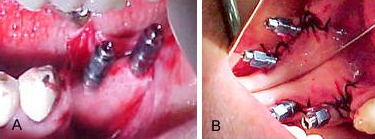

Figuras 8 A e B.

Na primeira fotografia vemos os implantes inseridos no tecido ósseo, em uma ótima posição e com excelente fixação no tecido. Os retalhos ainda não foram suturados. Na fotografia 8B, vemos a imagem no espelho dos retalhos suturados, criando condições para ser realizado a transferência de posição e preservando a gengiva aderida para o acabamento final das coroas.